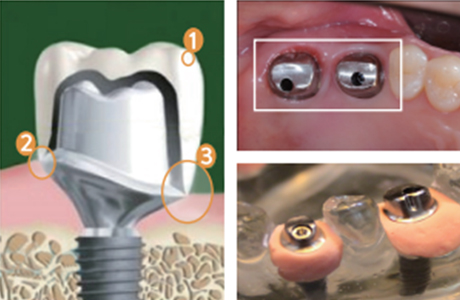

Abutment (지대주)

임플란트 뿌리와 머리를 연결하는 부위입니다.

Abutment(지대주)의 형태

기성 Abutment뿌리와 보철의 크기를 고려하여 만들어진 기성 형태의 어버트먼트

기성 Abutment뿌리와 보철의 크기를 고려하여 만들어진 기성 형태의 어버트먼트보편적으로 흔히 쓰이고 있는 기본 형태의 어버트먼트로 개인에게 맞추어진 형태는 아니기 때문에 사용함에 있어 불편함이 동반될 수 있습니다.

맞춤형 Abutment환자의 개인 구강구조를 고려하여 만들어진 개인 맞춤(커스텀) 형태의 어버트먼트

맞춤형 Abutment환자의 개인 구강구조를 고려하여 만들어진 개인 맞춤(커스텀) 형태의 어버트먼트환자 개개인의 구강구조에 맞춘 커스텀형 어버트먼트로 구강구조에 딱맞는 형태이기 때문에 사용함에 있어 불편이 덜하며 틈이 없는 밀착력으로 음식물 끼임 등의 문제도 적습니다.